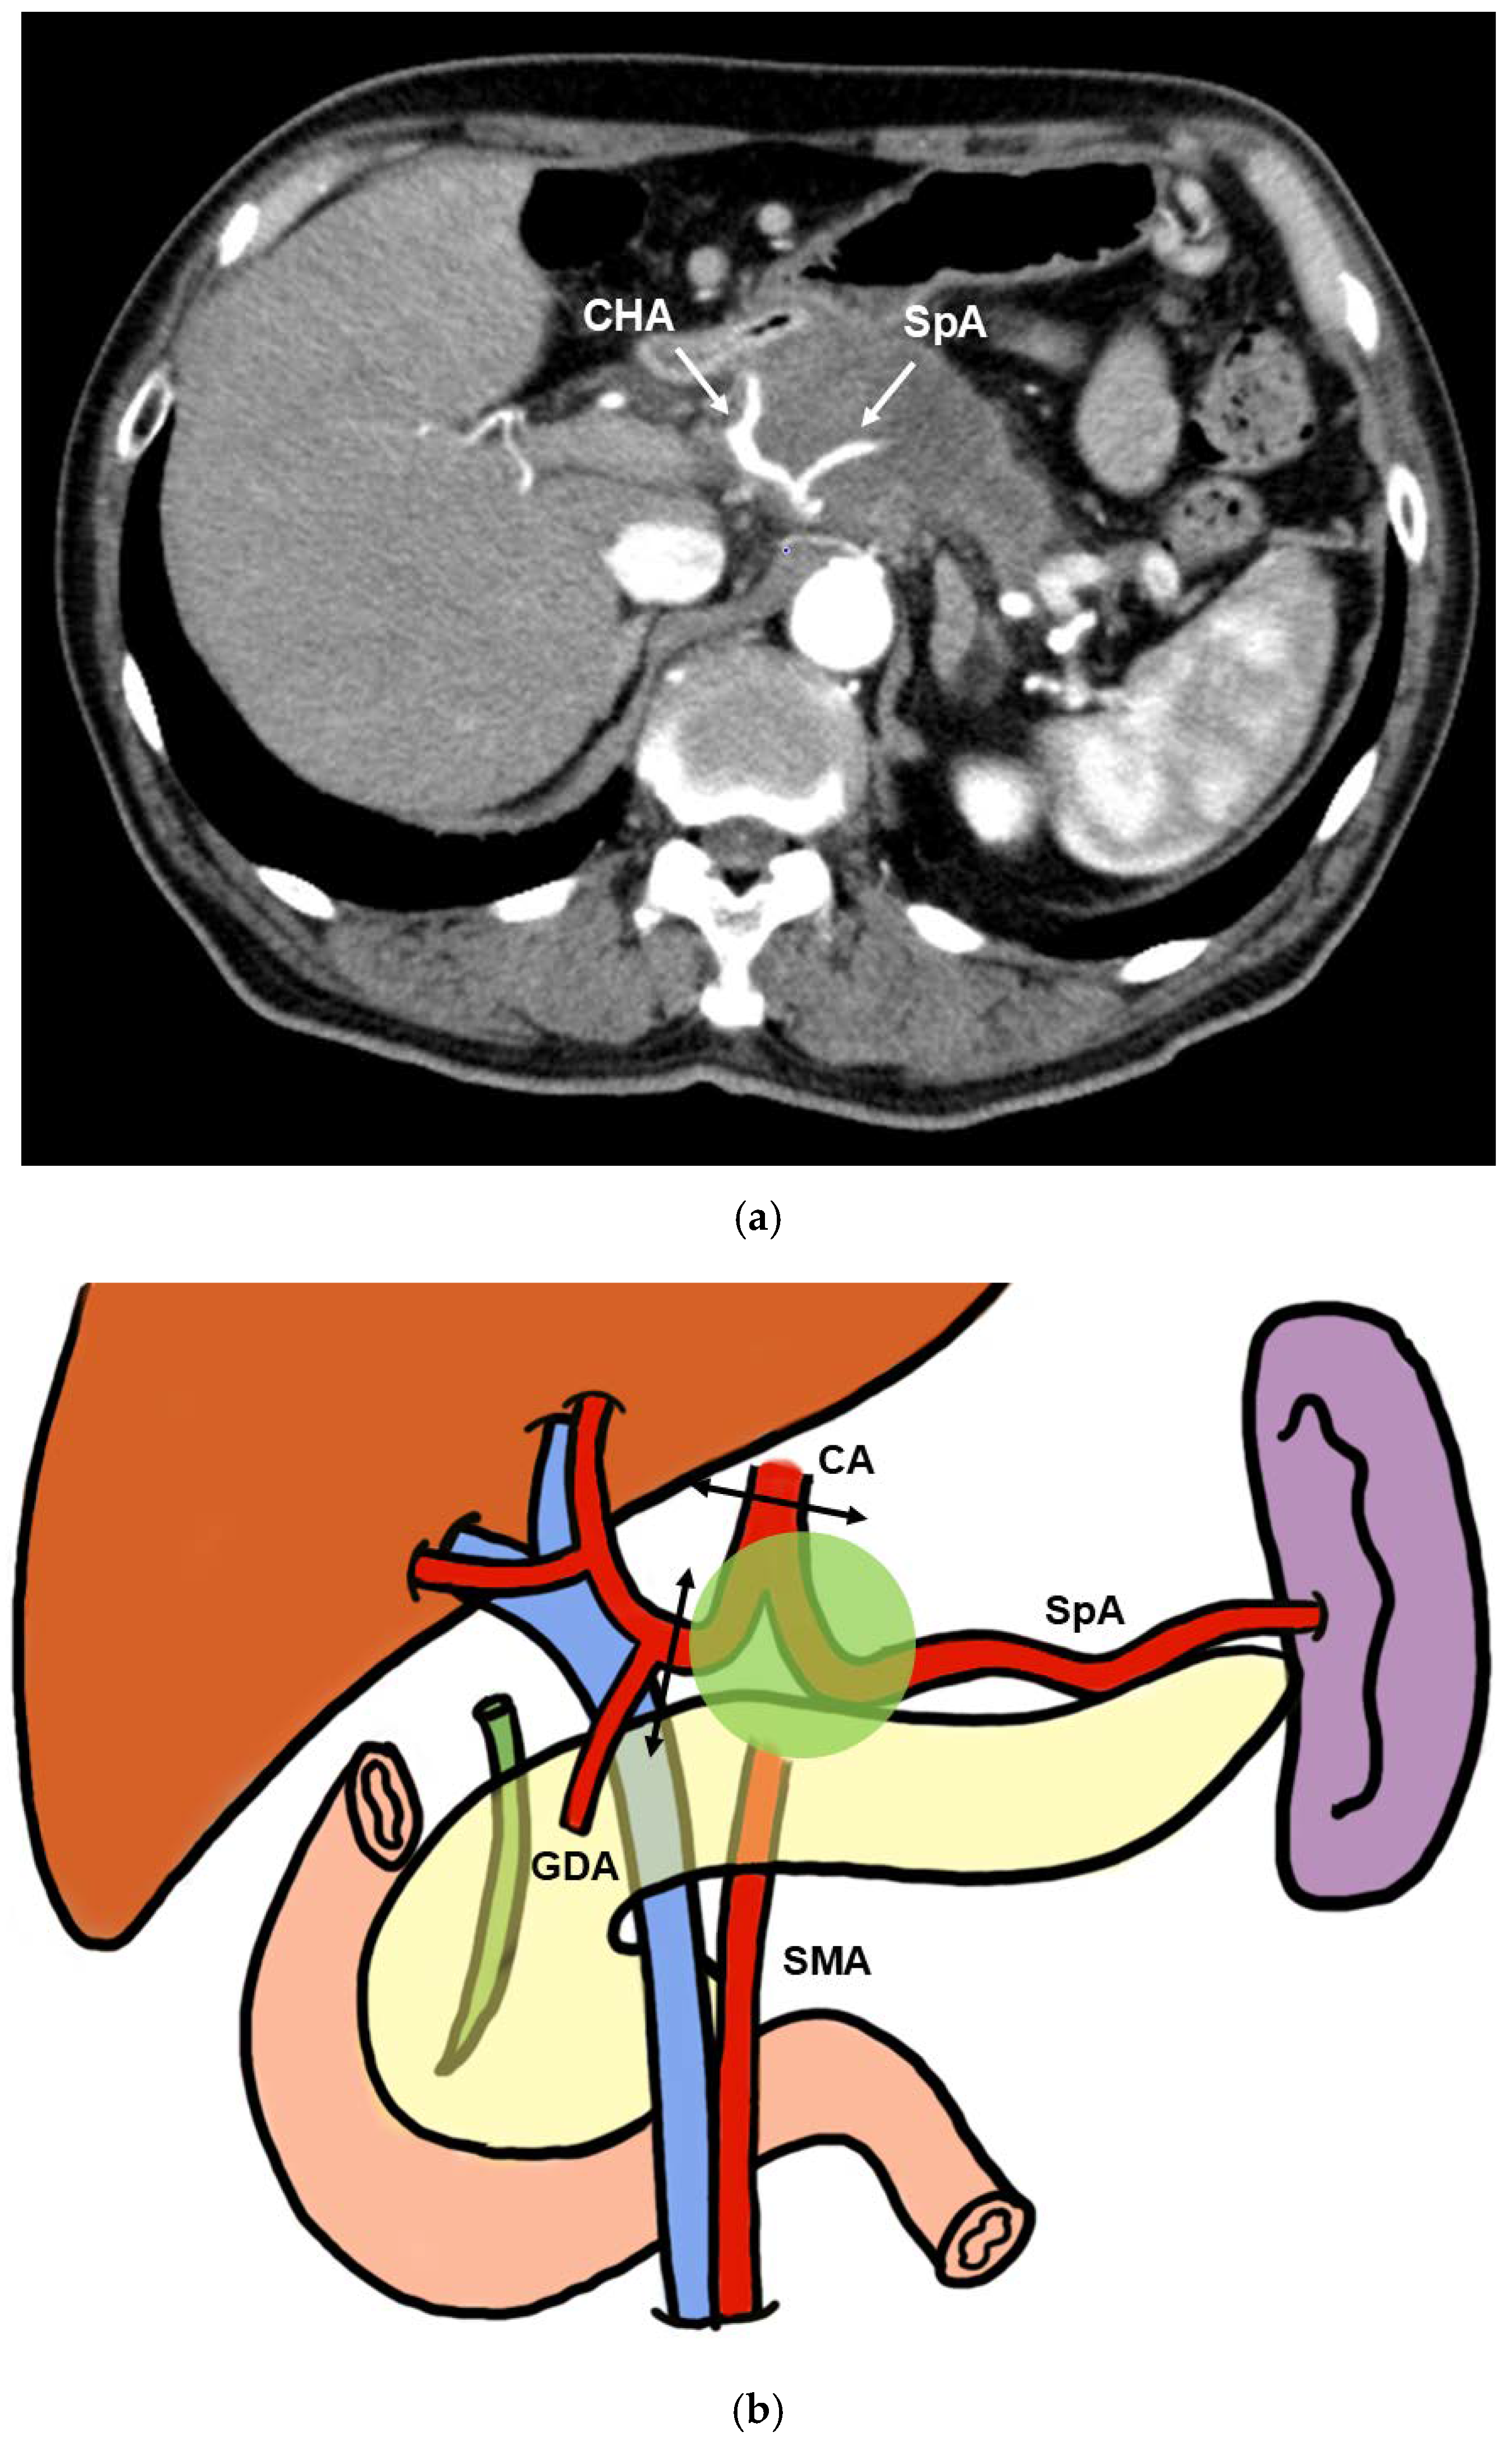

Classification of CA Resection and Reconstruction Pancreatectomy

2.3. CA Resection and Reconstruction

CA Reconstruction in TP-CAR+TG

CA Reconstruction in PD-CAR and TP-CAR(Spleen Preserving)